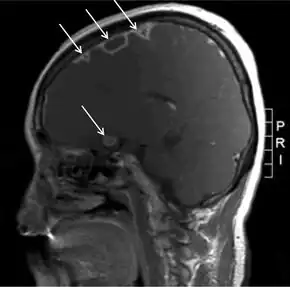

Thrombosis of the internal jugular vein can be displayed with sonography. Thrombi that have developed recently have low echogenicity or echogenicity similar to the flowing blood, and in such cases pressure with the ultrasound probe show a non-compressible jugular vein - a sure sign of thrombosis. Also color or power Doppler ultrasound identify a low echogenicity blood clot. A CT scan or an MRI scan is more sensitive in displaying the thrombus of the intra-thoracic retrosternal veins, but are rarely needed.